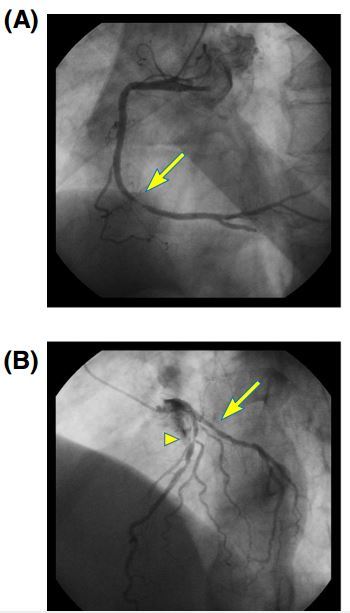

2019-03-14 08:23 673 心肌梗死 支架内血栓形成 PCI 最新资讯 临床综述 经典病例 佐他莫司 依维莫司 阿司匹林 氯吡格雷 沙格雷酯

以下是一例来自日本荒尾市医院的病例,患者多次出现恼人的支架内再狭窄,真相到底是什么?文章于2015年3月发表在International Journal of Cardiology 杂志。…